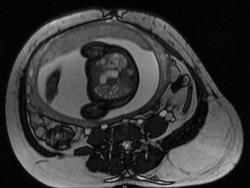

Иниэнцефалия представляет собой летальный сложный порок развития, возникающий в результате несмыкания нервной трубки. Для него характерно отсутствие части или всей затылочной кости со значительным расширением большого затылочного отверстия, в результате чего большая часть головного мозга располагается в области задней черепной ямки и частично в верхнем отделе позвоночного канала. В связи с этими анатомическими нарушениями верхняя часть позвоночника укорачивается и расщепляется и образуются энцефалоцеле и/или spina bifida. Характерным признаком иниэнцефалии является патологическое усиление лордоза. Иниэнцефалия относится к редким аномалиям с неустановленной этиологией, хотя сообщалось о возможном тератогенном генезе порока, чаще всего на фоне приема лекарственных препаратов в ранние сроки беременности (винбластин, стрептонигрин, трипаранол, тетрациклин, ампициллин). Более 90% пораженных плодов составляют девочки.

Пренатальная ультразвуковая диагностика иниэнцефалии во второй половине беременности основывается на обнаружении трех основных признаков: 1) дефекта затылочной кости; 2) расщепления позвоночного столба в верхней части; 3) фиксированного запрокинутого положения головы плода. Среди сочетанныхпороков центральной нервной системы при иниэнцефалии описаны анэнцефалия, микроцефалия, гидроцефалия, голопрозэнцефалия, аномалии задней черепной ямки, а из экстрацеребральных аномалий - диафрагмальная грыжа, омфалоцеле, деформации грудной клетки, пороки сердечнососудистой и мочеполовой систем, циклопия, расщелины лица, неперфорированный анус, косолапость и единственная артерия пуповины.